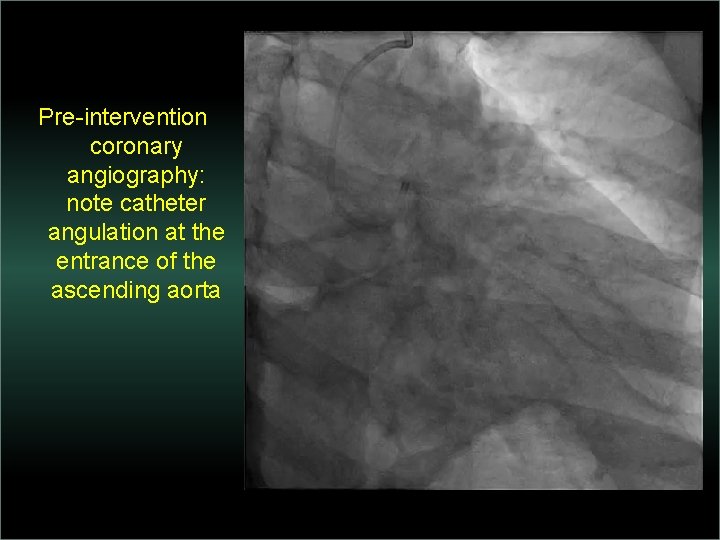

Transradial Interventions Difficult Anatomic Substrate Challenges and Solutions